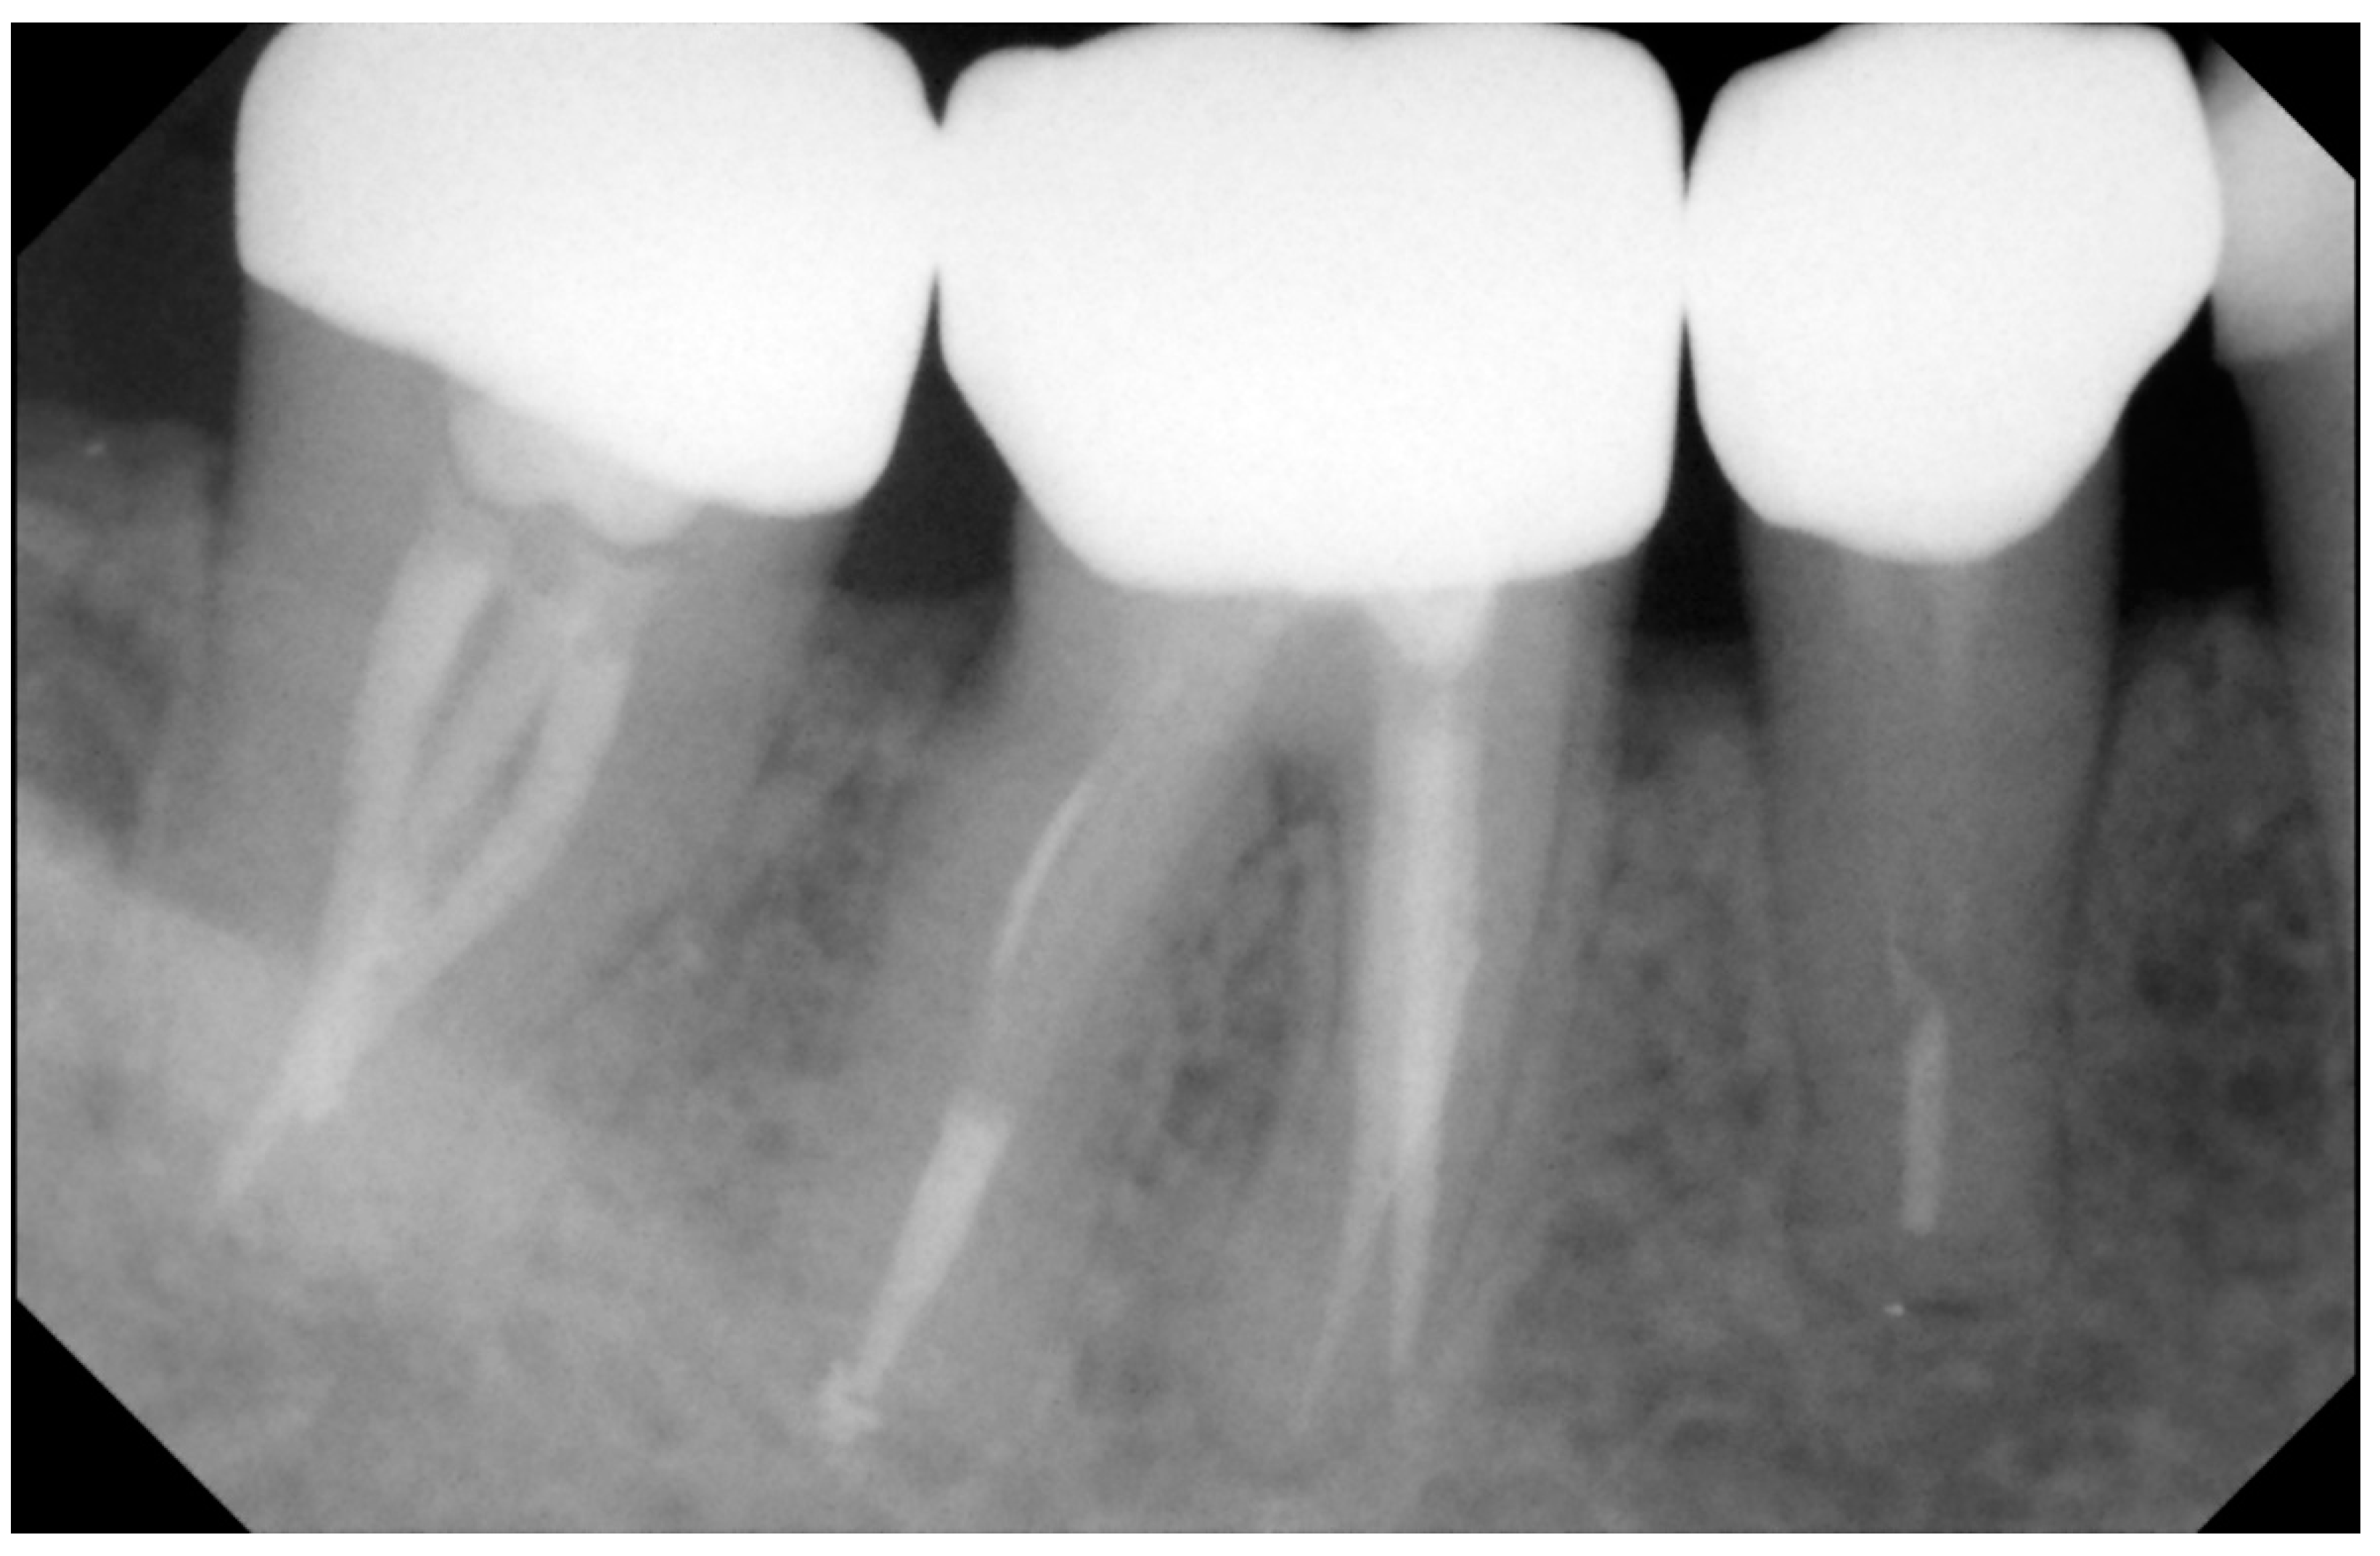

2. Materials and Methods